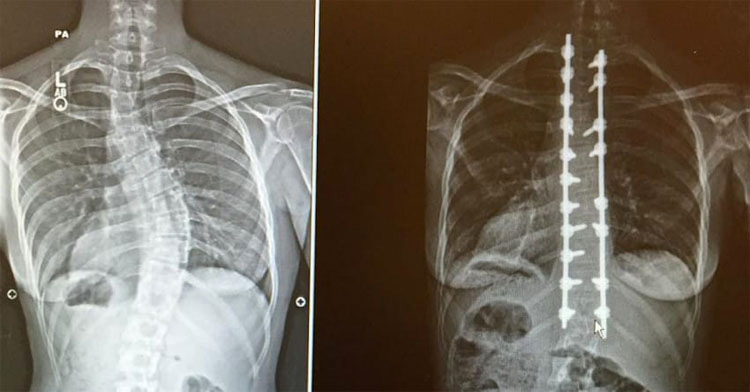

Con el paso del tiempo, el Dr. Thomas Errico, co-director del Spine Center de NYU, le diagnosticó el empeoramiento de la escoliosis como la causa de sus síntomas y le propuso que se sometiera a un tipo muy avanzado de cirugía de espalda.

El Dr. Errico dijo a Caroline que desde los 15 años de su diagnóstico inicial de escoliosis, la columna vertebral se había desplazado de una curvatura de 32 grados a una curvatura de 45 grados.

A continuación le dijo que finalmente tenía la necesidad de una cirugía para corregir este desplazamiento vertebral y aliviar su dolor crónico.